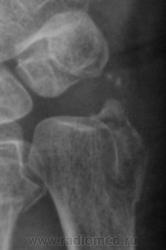

Какое мнение будет по поводу случая 2, особенно по поводу таранно-пяточного сочленения.

таранно-пяточном сочленения наблюдается подвывих.